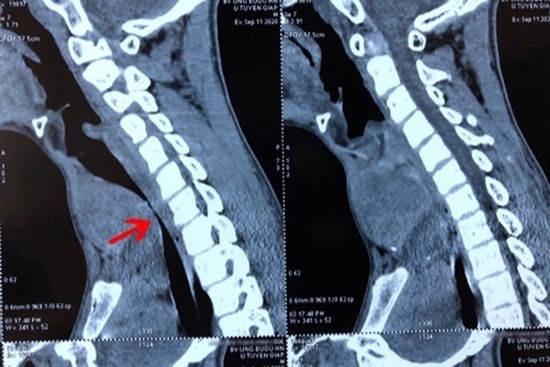

Sai lầm khiến bệnh nhi mắc ung thư tuyến giáp nguy kịch

Bệnh nhi được chẩn đoán u tuyến giáp cách đây 5 năm nhưng chỉ điều trị bằng thuốc nam.